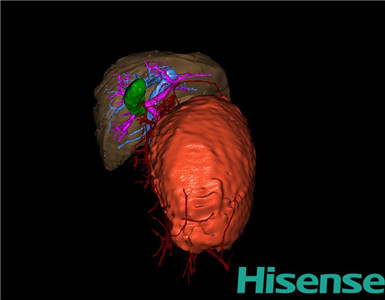

CT结果输入海信CAS系统后行3D重建及手术规划后,于2016-5-5全麻下行“腹膜后肿物切除术”手术治疗:

将0.625mm双源薄层CT资料的静脉期和动脉期Dicom格式文件导入海信CAS系统。

通过调节窗宽窗位调整CT序号,对肿瘤,肝脏,胆囊,下腔静脉,肿瘤,肝动脉、门静脉及肝静脉等进行三维重建;系统自动计算肿瘤体积和肝脏体积。

模拟手术操作,自动计算切除肿瘤体积。肝脏体积为425.6ml,肿瘤体积为971.8ml,肿瘤体积为肝脏体积的2.28倍,通过比对1-2岁正常肝脏体积为392.13±72.67ml,通过术前模拟手术,精准判断切除范围。

术前三维重建:

重建图片